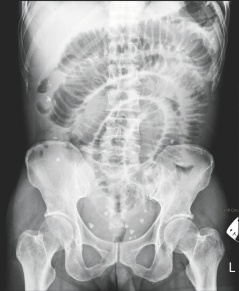

台南市55岁女子腹中取出29颗大大小小的“蛋”,从X光上可看到腹中满布点状的白色物体。

这名女子最近因腹痛、呕吐而到成大急诊就医,医师从X光检查中,发现腹腔内有许多白点状的物体,原本以为是粪石或食物堆积在肠道中,经紧急开刀,发现这些物体是在肠子外,而非肠子里,医师共取出大大小小共29颗,色白、外形椭圆,很像蛋一般,材质却像橡胶一般有弹性。

最大的直径约7厘米,最小2厘米,相当罕见。